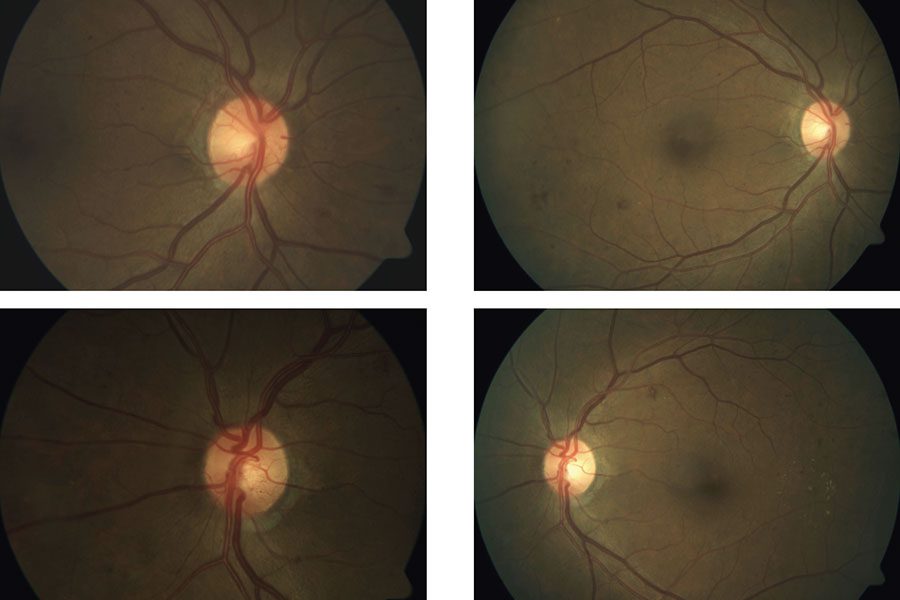

| Figura 1. Imágenes de un paciente varón de unos 30 años con diabetes tipo 2 mal controlada (hemoglobina A1c >12%) y sin atención ocular previa. La angiografía con fluoresceína en la cita inicial mostró áreas extensas de ausencia de perfusión periférica con frondas de neovascularización (se muestra el ojo izquierdo). La OCT mostró edema macular diabético grave que afecta al centro (arriba, a la derecha) que respondió bien a las inyecciones intravítreas de anti-VEGF (aflibercept) (abajo, a la derecha). Un año después de la presentación, tenía 20/20 en ambos ojos con una A1c <7% debido a una mejor adhesión al cuidado de la diabetes y un mejor control sistémico de la glucosa. Foto: Ian C. Han, MD. |